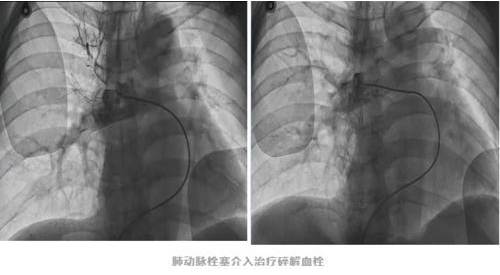

在与家属充分沟通后,心内科介入团队决定为他开展“肺栓塞局部溶栓与碎栓术”,也就是碎掉和溶解掉血栓,打通肺部血管。

手术时,医护人员需要穿上重达40斤的铅衣,在有辐射的射线下实施手术。经过一个半小时的手术,堵塞骆先生肺动脉主干的血栓被清除,肺部血流恢复,呼吸通畅,目前骆先生已痊愈出院。